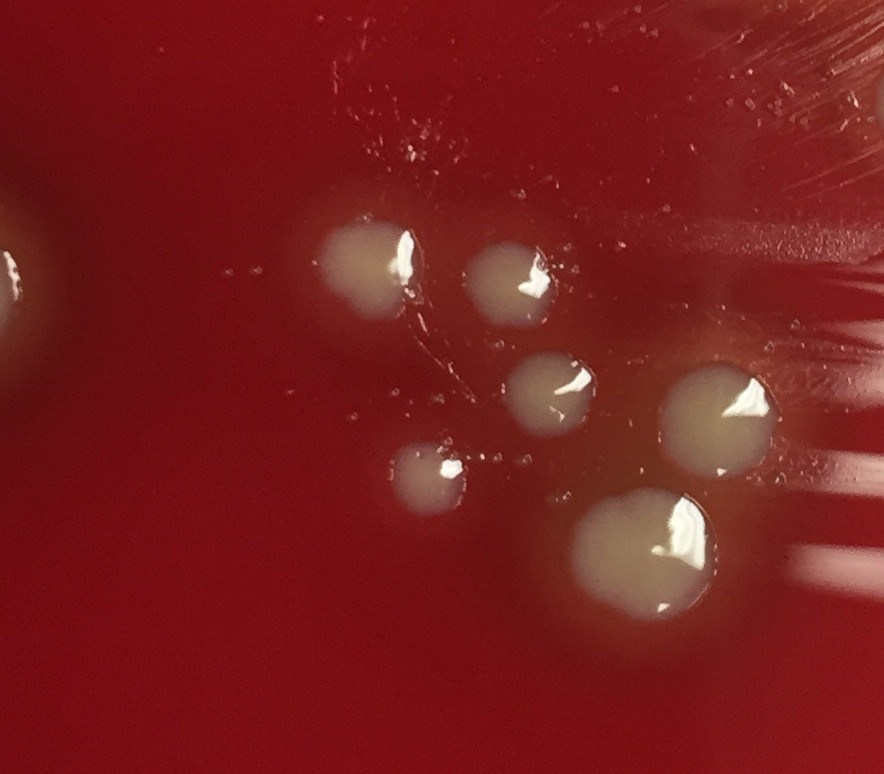

헤모필루스 인플루엔자는 X인자(헤민)와 V인자(니코틴아마이드 아데닌 다이뉴클레오타이드, NAD)가 추가된 초콜릿 한천배지에서 37°C, 이산화탄소가 풍부한 환경에서 배양한다.[90] 혈액 한천배지에서는 황색포도상구균, 폐렴구균과 같이 용혈성이 있는 세균들 주변에서만 위성처럼 성장한다. 집락은 볼록하고, 매끄럽고, 창백하며 회색이거나 투명하다.

성장을 위해 X 인자(헤민)와 V 인자(니코틴아마이드 아데닌 다이뉴클레오타이드, NAD)를 필요로 한다.[90] 혈액 한천배지에서 헤모필루스 인플루엔자는 황색포도상구균과 같이 용혈성이 있는 세균들 주변에서만 위성처럼 성장하는데, 이는 황색포도상구균이 용혈시킨 영역에서 V인자가 방출되기 때문이다.[90] 배양은 37°C 온도의 이산화탄소가 풍부한 배양기에서 초콜릿 한천배지를 이용한다.[90] 집락은 볼록하고, 매끄럽고, 창백하고, 회색이거나 투명한 색으로 나타난다.

- 세균 배양:

- 37°C 온도와 이산화탄소가 풍부한 환경에서 X인자(헤민)와 V인자(니코틴아마이드 아데닌 다이뉴클레오타이드, NAD)가 첨가된 초콜릿 한천배지를 사용한다.[90]

- 혈액 한천배지에서는 황색포도상구균, 폐렴구균과 같이 용혈성이 있는 세균 주변에서만 위성처럼 성장한다.[90] 이는 황색포도상구균이 헤모필루스 인플루엔자의 성장에 필요한 V인자를 방출하기 때문이다.[34]